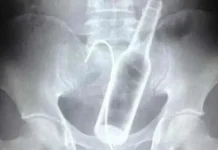

Homem enfia garrafa no ânus e objeto chega ao intestino

Um homem irariano de 50 anos foi levado ao hospital com dores abdominais, constipação e incapacidade de ir ao banheiro. Ao chegar no hospital...